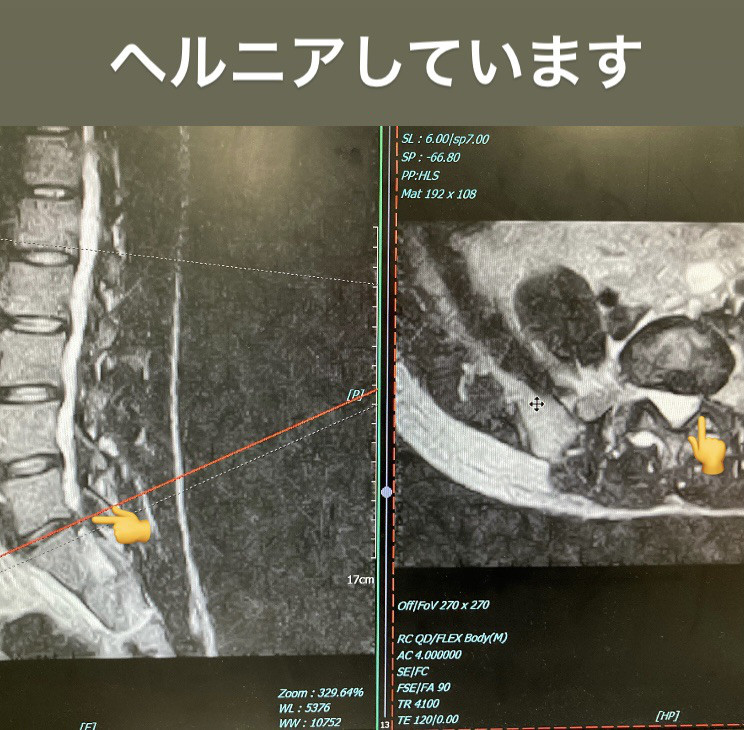

矢印のところが椎間板が痛んで炎症し痛みを引き起こしている場所です。

今日は腰椎5番目のヘルニアをした方が5ヶ月経っても症状が改善しないと言うのでリハビリしました。

主訴は脱力、評価をしたところL5の領域の前脛骨筋、長母趾伸筋の筋力が低く、

MMT(筋力テスト5がMAX)前脛骨筋が3、長母趾伸筋が4と低くなっていましたので神経の圧迫を解除する手技を行いました。

すると筋力は前脛骨筋4に回復し、長母指伸筋も4強に変わりました。

ヘルニアはほっといても治癒しますが、手を加えるとより回復しやすくなります。

患者さんも力がいきなり入るようになって「まるで手品みたい」と喜んでいただけてよかったです。